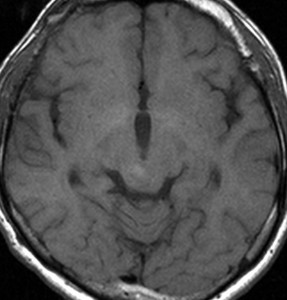

左はT1強調画像,右はFLAIR画像です。中脳視蓋が腫れて腫瘍がにじむように広がっているのがわかります。この腫瘍本体は15歳の時から21歳の時まで大きくなっていないので,中脳視蓋グリオーマ tectal gliomaの診断です。

T1強調ガドリニウム増強画像です。15歳の時は腫瘍の半分以上が強くガドリニウム増強されていましたが,この21歳の時の画像では,中心部やや右寄りに増強像が認められるだけです。この性質は,腫瘍が毛様細胞性星細胞腫であることを示しています。